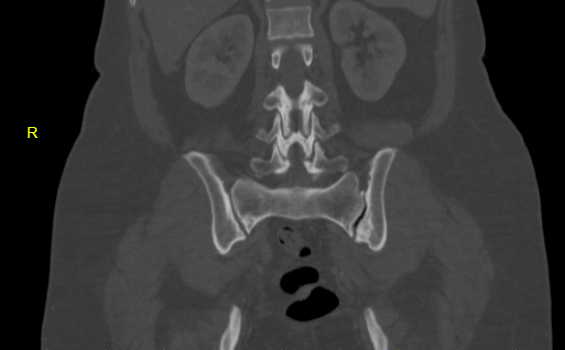

osteitis condenses ilii

Case of Left osteitis condenses ilii